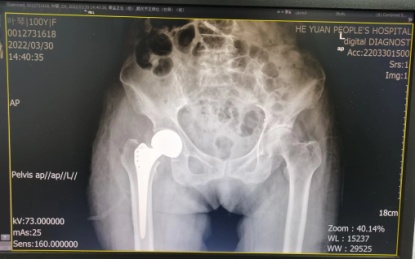

3月30日,经过充分的术前准备,在麻醉科手术室医护人员的精心“保驾护航”下,曾红生主刀、带领骨科二区团队为叶婆婆施行手术,手术过程顺利,仅耗时50多分钟就成功为百岁寿星老人完成半髋关节置换术。

术后骨盆正位